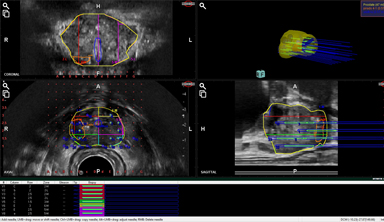

Overlap of US & MRI

prostate contouring

Automatic Elastic Fusion

Adopt mode

(manual adjustment)

Automated Contour Tracking

(real-time tracking with Prostate movements)

Prostate, Lesion & Urethra

3D solid model (4 windows)